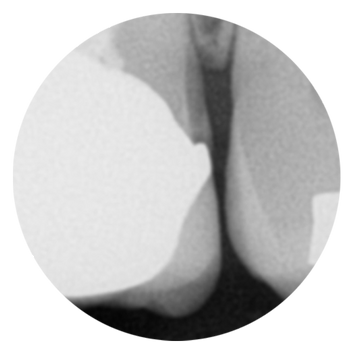

Traditional Digital X-Ray

DC AIR Digital X-Ray